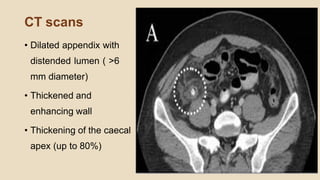

CT scans

• Dilated appendix with

distended lumen ( >6

mm diameter)

• Thickened and

enhancing wall

• Thickening of the caecal

apex (up to 80%)